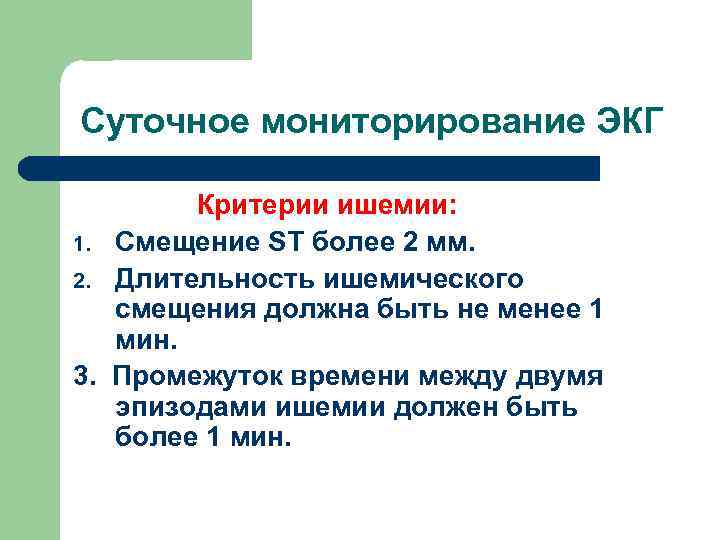

Суточное мониторирование ЭКГ Критерии ишемии: 1. Смещение ST более 2 мм. 2. Длительность ишемического смещения должна быть не менее 1 мин. 3. Промежуток времени между двумя эпизодами ишемии должен быть более 1 мин.